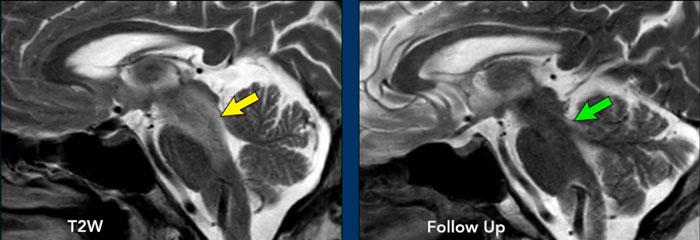

Các hình ảnh này thuộc về một nam bệnh nhân 62 tuổi nhập viện vì liệt dây thần kinh vận nhãn (dây III) bên trái.

Hình ảnh

Chuỗi xung FLAIR cho thấy tăng tín hiệu lan rộng ở cầu não và trung não.

Có hình ảnh ngấm thuốc dạng chấm và dạng tuyến tính.

Khi kết hợp các điểm ngấm thuốc ở các mức độ khác nhau, có thể nhận thấy đây thực chất là một phần của kiểu ngấm thuốc tuyến tính hoặc quanh mạch máu.

Chẩn đoán phân biệt:

- Các hình ảnh này gợi ý CLIPPERS, mặc dù đáp ứng với corticosteroid chỉ có thể được đánh giá sau khi điều trị.

- Hội chứng hủy myelin thẩm thấu vùng cầu não thường có vị trí trung tâm hơn.

- Thiếu máu cục bộ biểu hiện khuếch tán hạn chế và không có ngấm thuốc quanh mạch máu.

Tiếp tục xem hình ảnh sau điều trị của bệnh nhân này…

Bệnh nhân này được điều trị bằng corticosteroid và hình ảnh ngấm thuốc quanh mạch máu không còn được ghi nhận trên phim chụp theo dõi.

Tiếp tục xem các lát cắt sagittal…

Trên chuỗi xung T2W lát cắt sagittal, vùng tăng tín hiệu (mũi tên vàng) cũng đã biến mất trên hình ảnh theo dõi (mũi tên xanh lá).